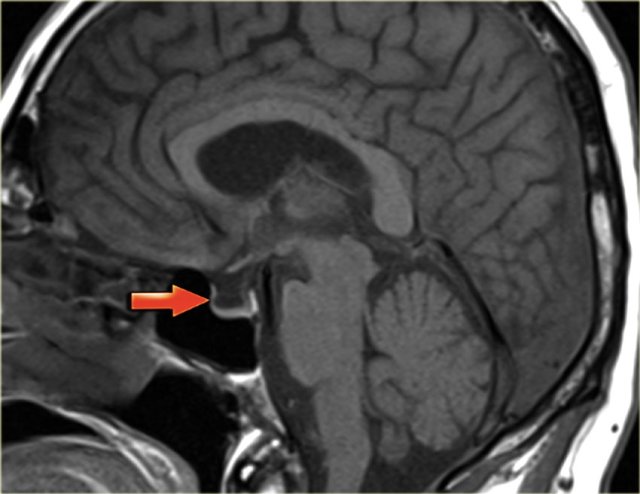

Thrombosis and increased CSF pressure

In some patients dural sinus thrombosis may, even after recanalisation, lead to persisting disturbances in venous circulation.

This may lead to raised intracranial CSF pressure as assessed by lumbar puncture.

Clinically, these patients complain of headaches and they may have vision disturbances due to papil edema.

On MRI, one may see increased CSF around the optic nerve and an empty sella.

Apparently in some patients a residual stenosis persists.

On the left a T2-weighted image demonstrating papil edema and an empty sella.

Continue with the sagittal T1-weighted image.

Here the sagittal T1-weighted image demonstrating the empty sella (arrow).

It is called an empty sella because the sella is mainly filled with CSF as the hypofysis is compressed downwards due to the increased intracranial pressure.